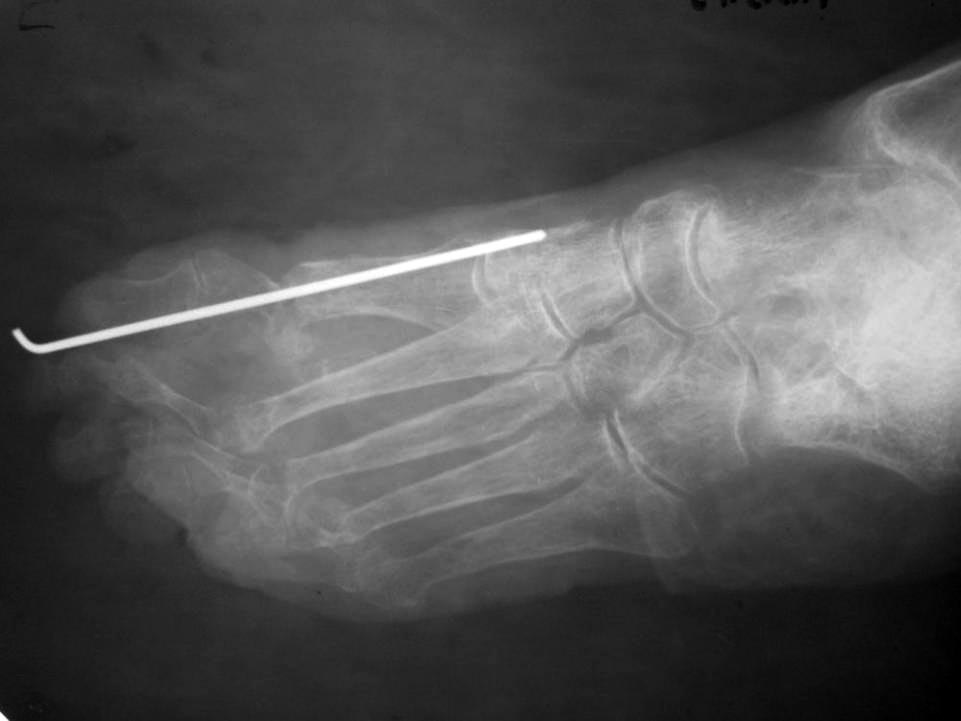

Пациентке выполнен артродез 1-ого плюснефалангового сустава, резекции

говок 2-3 плюсневых костей, субкапитальная остеотомия 4 плюсневой кости,

тенотомиии разгибаталей 2-5 п. стопы. Раны зажили первичным натяжением.